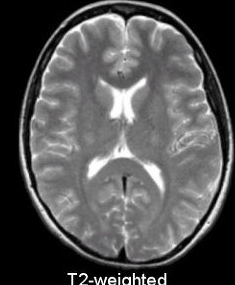

2018년 10월에 뇌 MRI 보험적용이 바뀌게 됩니다. 2018년 10월 이전에는 중증 뇌질환환자로 의사가 인정하는 경우에만 제한적으로 건강보험 적용이 되었습니다. 해당 상병으로는 뇌출혈, 외전증, 뇌경색 등이 있습니다.

하지만 2018년 10월에는 뇌혈관 및 뇌 MRI 가 건강보험 적용이 확대 되었습니다. 경증인 뇌질환이나 신경학적으로 이상이 있거나, 검사상 이상소견이 있다면 건강보험이 적용이 가능해졌습니다.

그리고 뇌질환이 의심되는 두통이 있거나, 어지러움이 있고 신경학적 검사를 실시한 경우에도 건강보험이 적용이 되어서 많은 국민들의 부담이 줄어들었습니다.